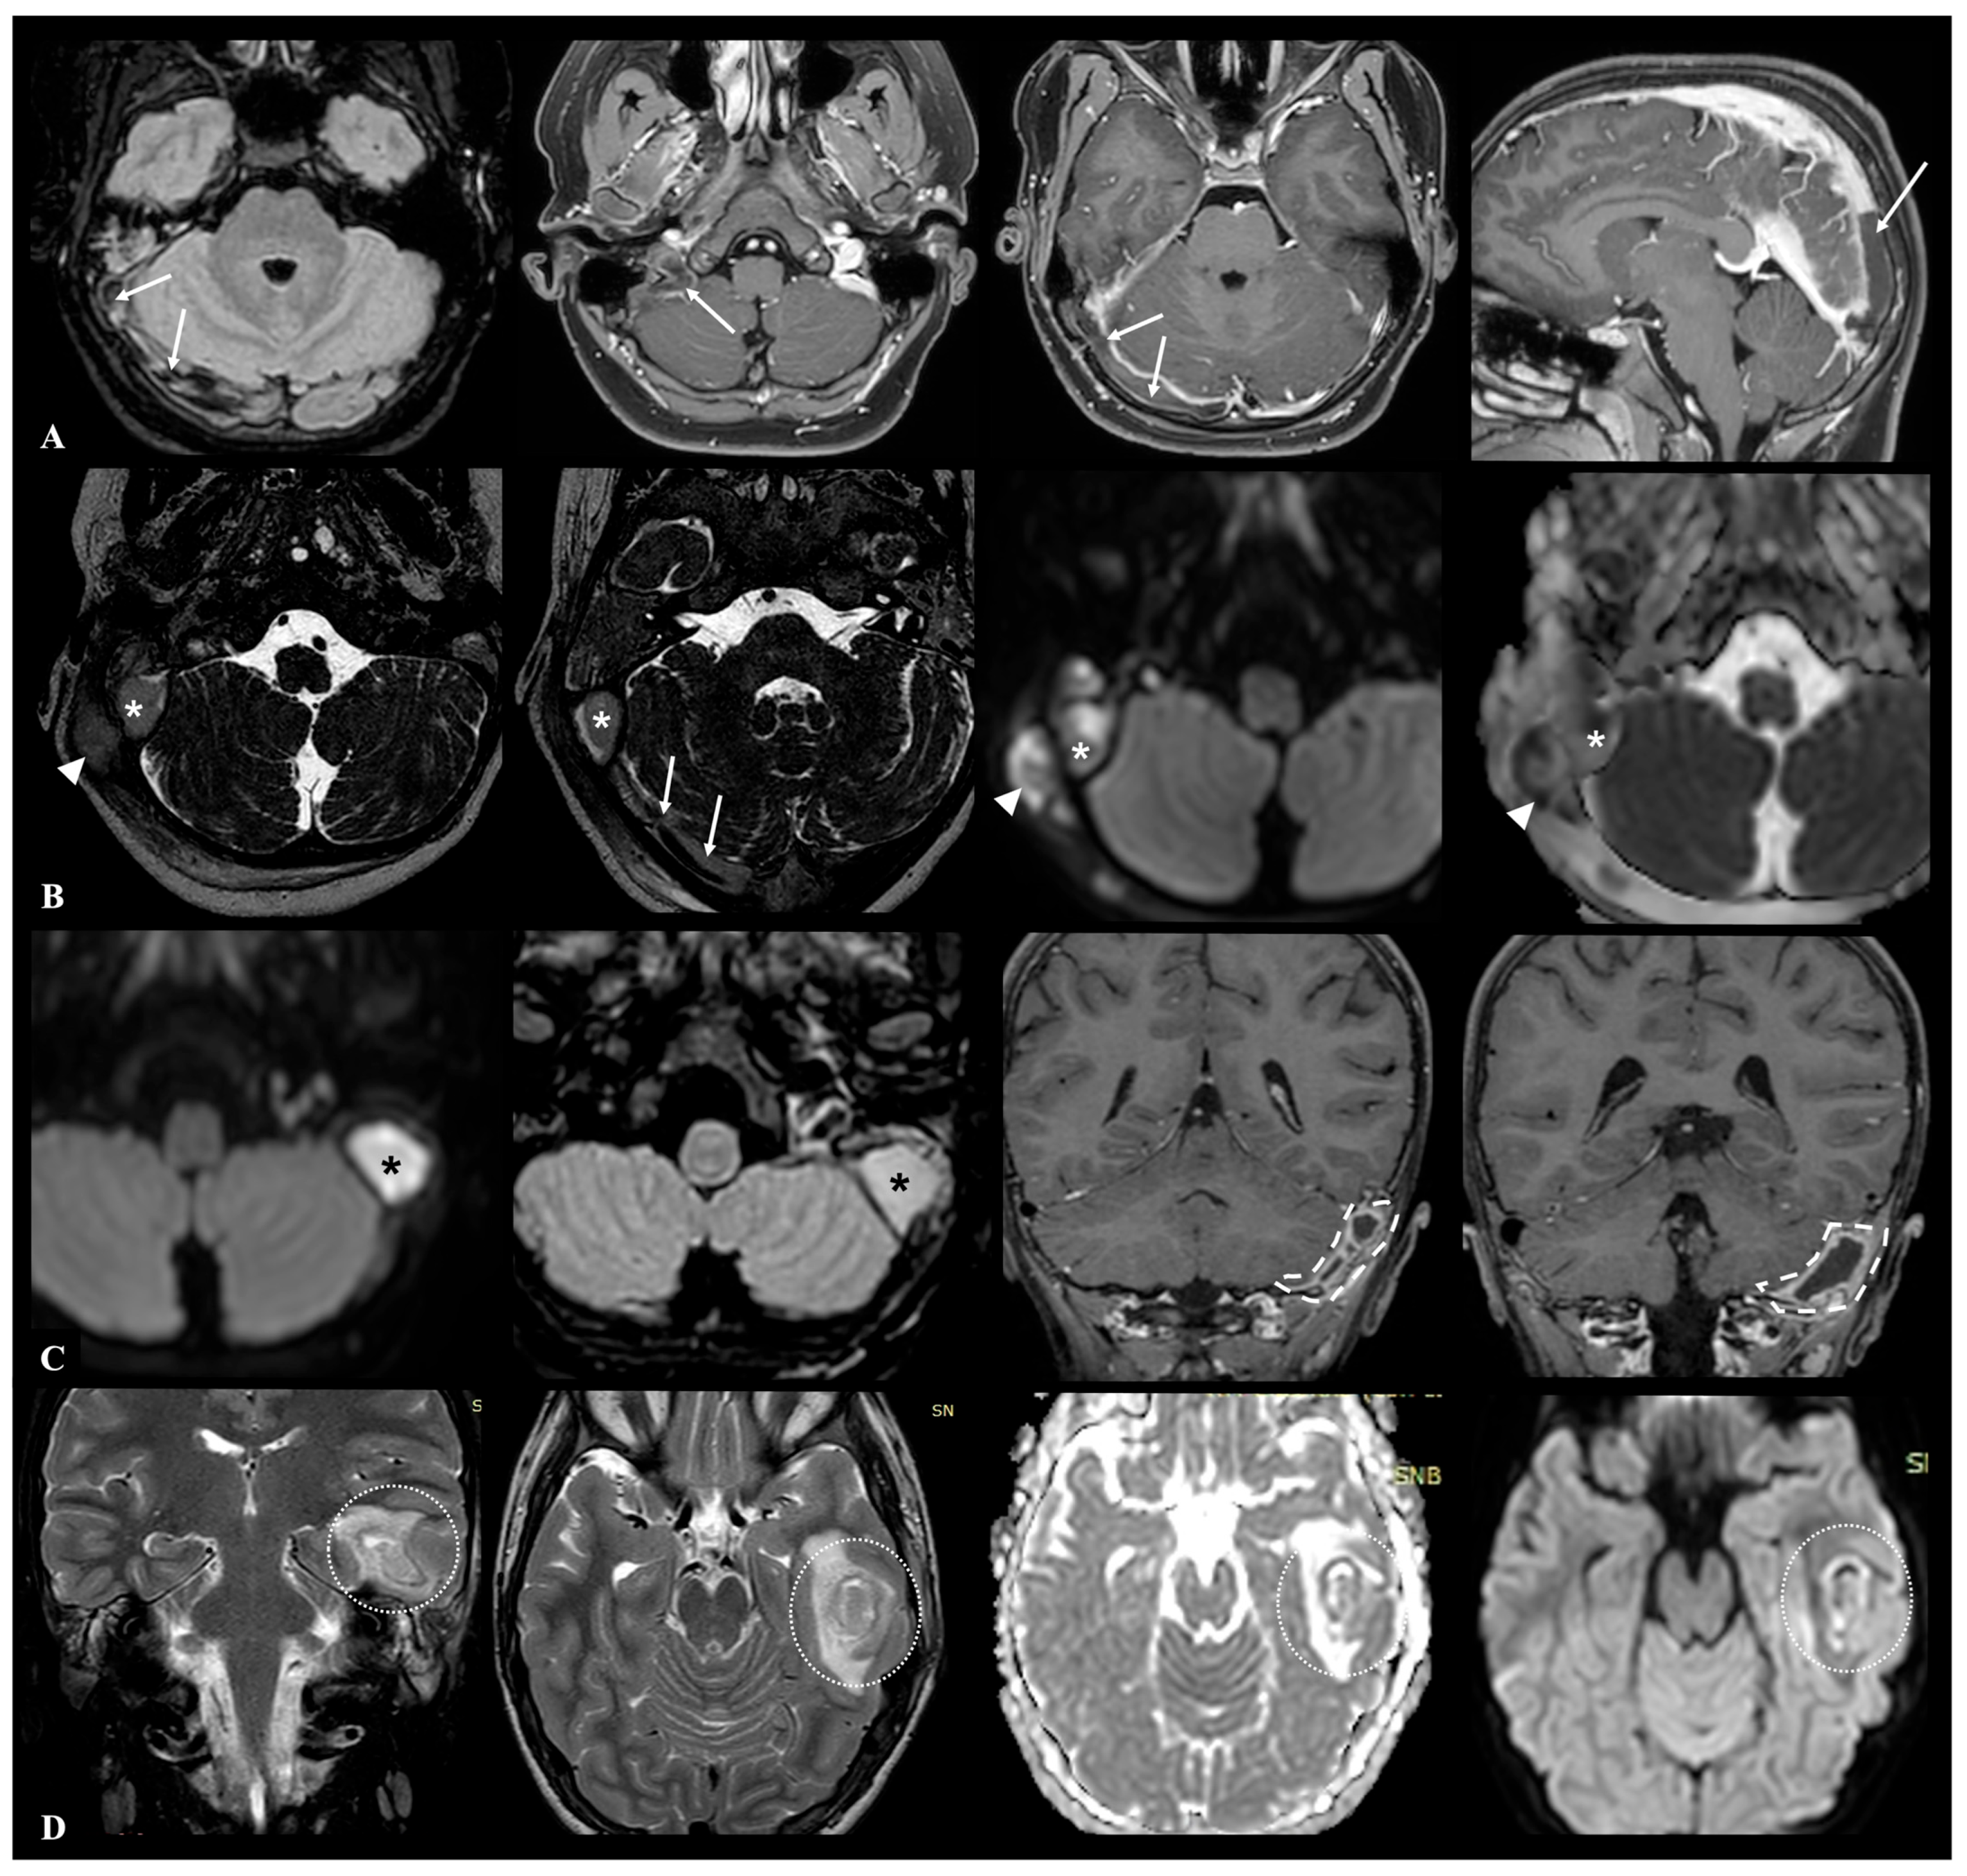

Acute otomastoiditis (AOM) is an infectious condition involving both the middle ear and the mastoid air cells, and it represents the most frequent secondary site of involvement in acute otitis media [1,2]. While most cases resolve without sequelae following appropriate antibiotic therapy, a small proportion may progress to complicated forms with extension of the infection to adjacent structures. These complications, which are broadly categorized as intracranial and extracranial, are associated with significantly increased morbidity, and require prompt recognition and management to prevent serious or permanent outcomes [3]. Intracranial complications, though relatively rare—with an estimated incidence ranging from 0.2% to 2%—are particularly severe and potentially life-threatening [4]. These include thrombosis of the transverse-sigmoid-jugular venous complex, meningitis, epidural empyema, subdural empyema, brain abscess, and in some cases secondary hydrocephalus [5]. An example of possible intracranial complications during AOM is shown in Figure 1.

Figure 1. MRI examples of the major possible otogenic intracranial complications in pediatric AOM patients: row (A) thrombosis of the transverse-sigmoid-jugular venous complex extending to superior sagittal sinus (white arrows) in a 13-year-old male patient with right-sided ACOM; row (B) right-sided ACOM in a 7-year-old female patient, with both extracranial extension (retromastoid abscess located beneath the proximal insertion of the sternocleidomastoid muscle—white arrowheads) and intracranial extension (epidural empyema of the posterior cranial fossa—white asterisks—associated with severe flow reduction in the transverse sinus—white arrows—and meningeal thickening); row (C) left-sided posterior cranial fossa subdural empyema (white dashed lines) in a 5-year-old male patient with large otomastoid abscess (black asterisks) and meningeal thickening; row (D) left middle cranial fossa brain abscess (white dotted circles) involving the temporal lobe secondary to ACOM in a 4-year-old female patient.